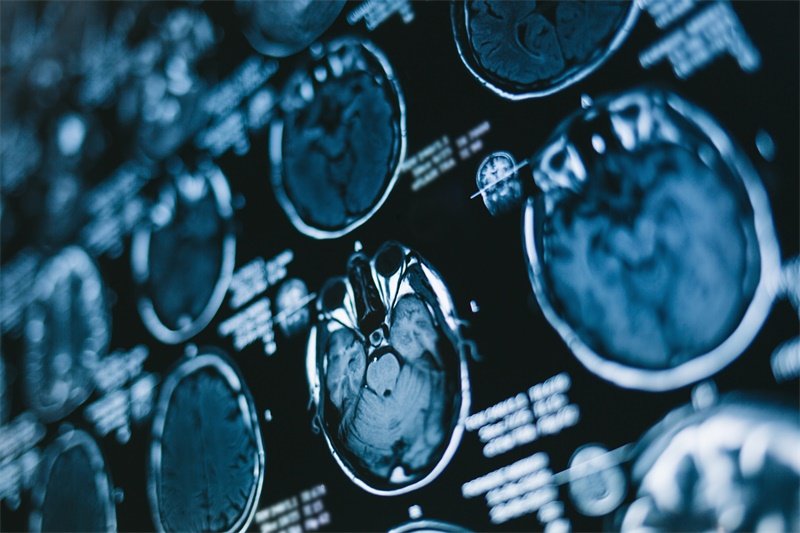

影像学检查

影像学检查是诊断垂体窝占位病变的重要工具。常用的方法包括磁共振成像(MRI)和计算机断层扫描(CT)。这些影像学手段可以帮助医生观察垂体窝的大小、形状及周围结构的变化。